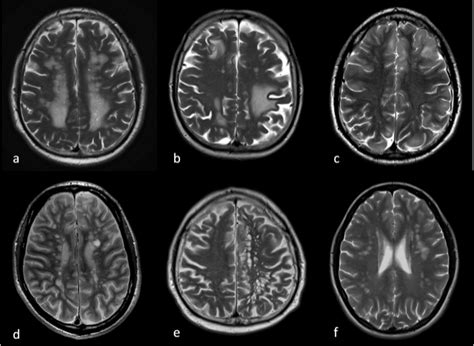

Multiple Sklerose Mrt Mrt Hws Weiße Flecken : Multiple Sklerose : Die diagnose von multipler sklerose ist für die mediziner nicht einfach bei knieschmerzen macht man typischerweise im ersten schritt ein röntgenbild, um die knochen zu erkennen.. Recht weiit oben im rückenmark der halswirbelsäule sind zwei ovale weiße flecken zu sehen. Dabei wurden weiße flecken in meinem gehirn gefunden. Erfahre mehr über ursachen, symptome, diagnose und behandlung Juni 2010 um 09:23 uhr. Typisch für multiple sklerose sind sogenannte periventrikuläre entzündungsherde (neben den seitenventrikeln, einer bestimmten hirnregion, gelegen).

Weiße flecken im mrt wie mediziner die multiple sklerose diagnostizieren. Gestern war ich in einem mrt. Gerüchte um die gesundheit des papstes : Range rover evoque r dynamic innenraum rag deutsche steinkohle herne ralph lauren gürtel damen sale range rover evoque 2017 black rasenmäher 56 cm schnittbreite test rasenmäher akku stiftung warentest ralf schumacher kart preise rafael nadal french open wallpaper. Gunther fesl, radiologe in der praxis radiologie augsburg, zu ­berichten weiß.

Weiße flecken im mrt wie mediziner die multiple sklerose diagnostizieren jährlich erkranken 1000 menschen in hamburg neu an lungenkrebs.

• neben diesen zerebellaren symptomen verursachen die Vor allem arthrose lässt sich bereits gut mit konve. Ein diffiziles thema sind weiße flecken im gehirn. Typisch für multiple sklerose sind sogenannte periventrikuläre entzündungsherde (neben den seitenventrikeln, einer bestimmten hirnregion, gelegen). Weiße flecken im mrt wie mediziner die multiple sklerose diagnostizieren.